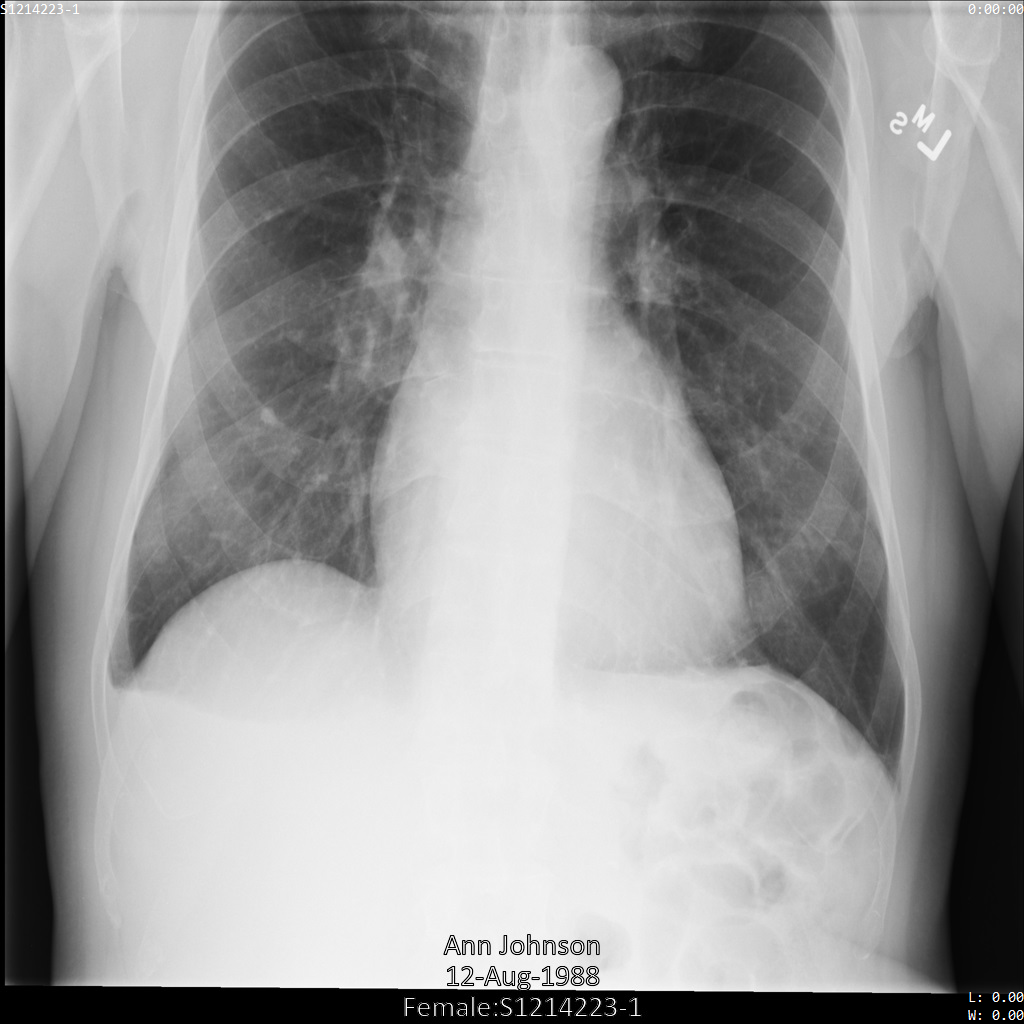

In jedem der folgenden Abschnitte finden Sie Beispiele zur De-Identifikation von DICOM-Daten mithilfe verschiedener Methoden. Für jedes Beispiel wird eine Ausgabe des de-identifizierten Images bereitgestellt. In jedem Beispiel wird das folgende Originalbild als Eingabe verwendet:

Sie können das Ausgabebild jedes De-Identifizierungsvorgangs mit diesem Originalbild vergleichen, um die Auswirkungen des Vorgangs zu sehen.

Nachdem Sie das Image an die Cloud Healthcare API gesendet haben, wird es wie folgt angezeigt. Während die Metadaten, die in den oberen Ecken des Bildes angezeigt werden, entfernt wurden, bleiben die eingebrannten geschützten Gesundheitsinformationen (PHI) unten im Bild erhalten. Informationen zum Entfernen des eingebrannten Texts finden Sie unter Eingebrannten Text aus Bildern entfernen.